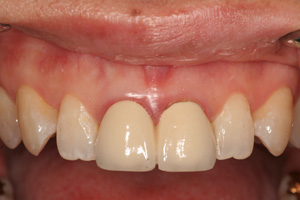

Clinical Cases